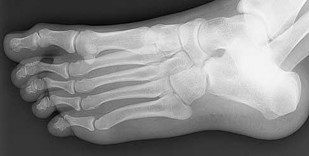

A 30-year-old female sustains a midfoot injury after falling from a horse. Radiographs demonstrate diastasis between the bases of the 1st and 2nd metatarsals. In a normal anatomic state, the native Lisfranc ligament originates and inserts on which two bony structures?

Correct Answer: Lateral aspect of the medial cuneiform to the medial aspect of the base of the 2nd metatarsal

Explanation:

The Lisfranc ligament is a stout, obliquely oriented intra-articular ligament that acts as the primary stabilizer of the second tarsometatarsal joint complex. It connects the lateral aspect of the medial cuneiform to the medial aspect of the base of the second metatarsal. Importantly, there is no direct ligamentous connection between the bases of the first and second metatarsals.